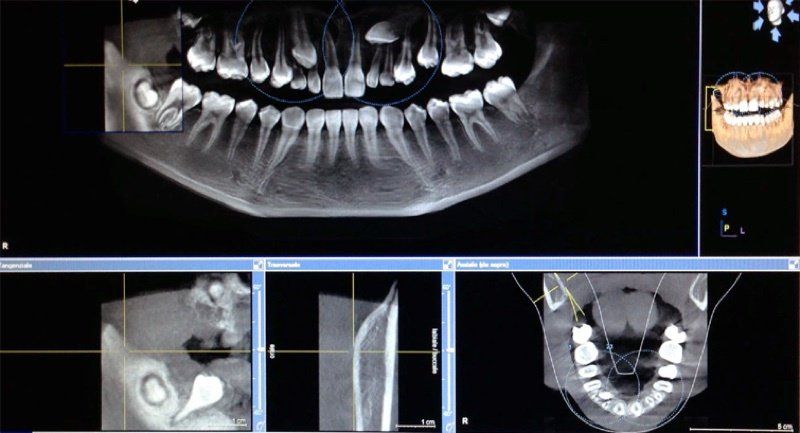

- tac Dentascan “Cone Beam” 3D (CBCT);